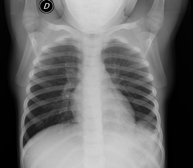

- RX Tórax

Técnica mediante la cual, utilizando rayos X, se obtienen imágenes de la caja torácica (corazón, pulmones, arcos costales, clavículas, etc.) para su estudio. - RX Esternón

- Chest X-ray

A chest X-ray uses a small dose of radiation to obtain a two-dimensional image of the thoracic cavity and its contents (lungs, heart, mediastinum, etc.). It is one of the most commonly performed medical tests.